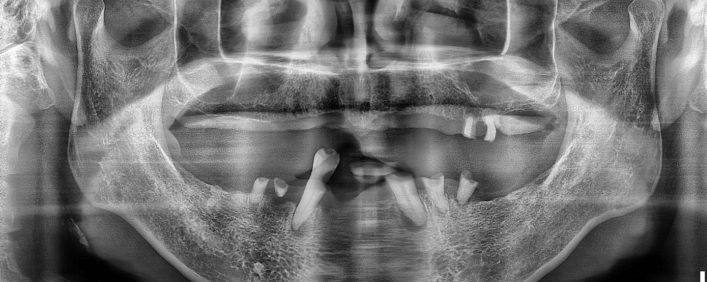

임플란트 치료사례

서울스마트치과는 결과로 증명합니다.

위 치료 사례는 서울스마트치과에서 직접 치료를 받고, 환자 본인의 동의를 얻어 게재된 사진으로 무단 인용, 도용, 재배포 시 민/형사상 책임을 질 수 있습니다.